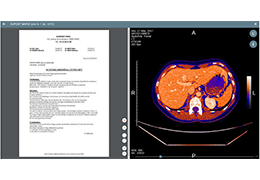

View X-Ray CT & MRI Scans Fast and Easily

FREE and easy to use 3D DICOM Viewer – for surgeons and patient education

Multi-planar slicing.

Side-by-side comparative assessment for pre- and post-operative scans.